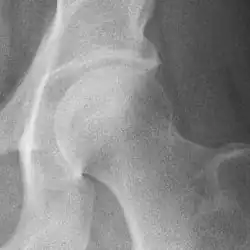

Hip

Hip joint with no signs of osteoarthritis.

The most commonly used radiographic classification system for osteoarthritis of the hip joint is the Kellgren–Lawrence system (or KL system).[6] It uses plain radiographs.

Osteoarthritis of the hip joint may also be graded by Tönnis classification. There is no consensus whether it is more or less reliable than the Kellgren-Lawrence system.[8]

Severe (Tönnis grade 3) osteoarthritis of the hip.

Tönnis classification[9]

Grade Description

0 No osteoarthritis signs

1 Mild:

• increased osteosclerosis

• minor joint space narrowing (normal joint space is at least 2 mm at the superior acetabulum)[7]

• no or minor loss of head sphericity

2 Moderate:

• small bone cyst

• moderate joint space narrowing

• moderate loss of head sphericity

3 Severe:

• large bone cysts

• severe joint space narrowing, or joint space obliteration

• severe deformity of the head